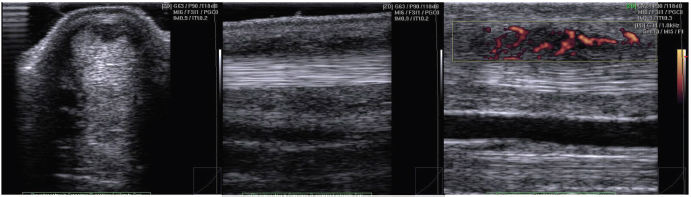

All tendon lesions of horses of group L showed intratendinous vascularization. Mean PD signal of the ill-defined area within the SDFT was 2.48 ± 0.65 with the PDFG scale, while 3.4 ± 0.82 with PDOH scale (Fig. 2).

Fig. 2. Representative US images of an injured tendon showing intratendinous vascularization. PD signal has been scored in FG 3.

In our study, tendons with clinical and ultrasonographic signs of tendinopathy (group L), have an increased PD score and PD signal is not only visible in the interfascicular zone but also within the tendon lesion (intratendinous zone) (Fig. 2). A validated neovascularization score is essential in the evaluation of tendinopathy, and future studies can be focused on the interobserver and intraobserver reliability.